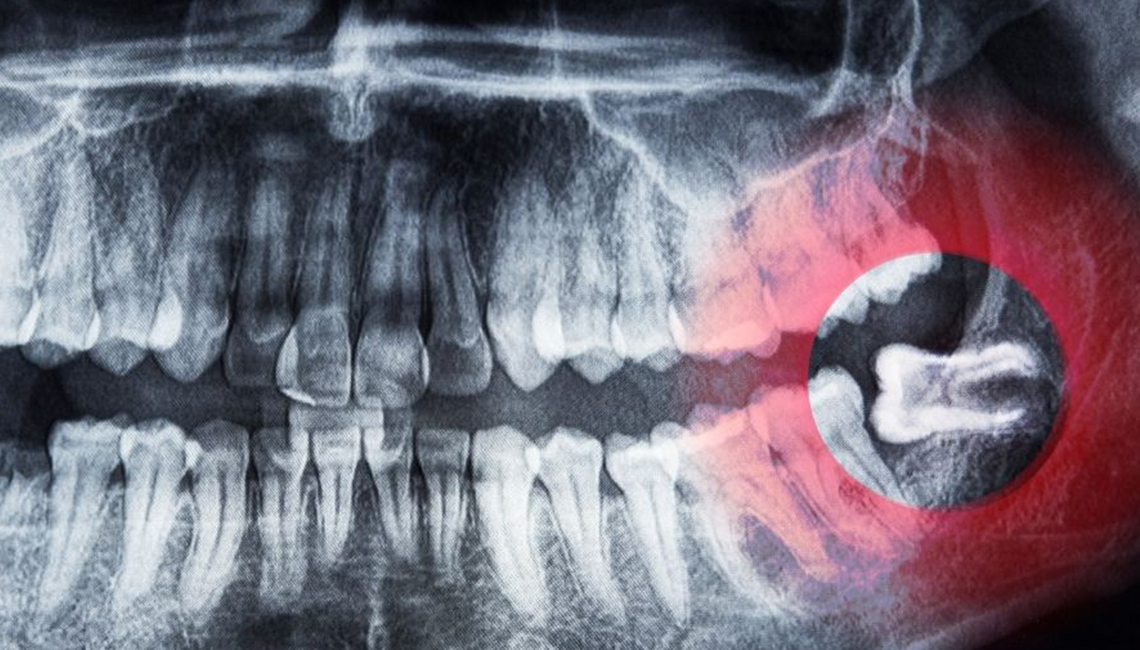

1. At the first consultation visit, the doctor takes a pantomographic picture, thanks to which he can see the position of the tooth and the course of its roots